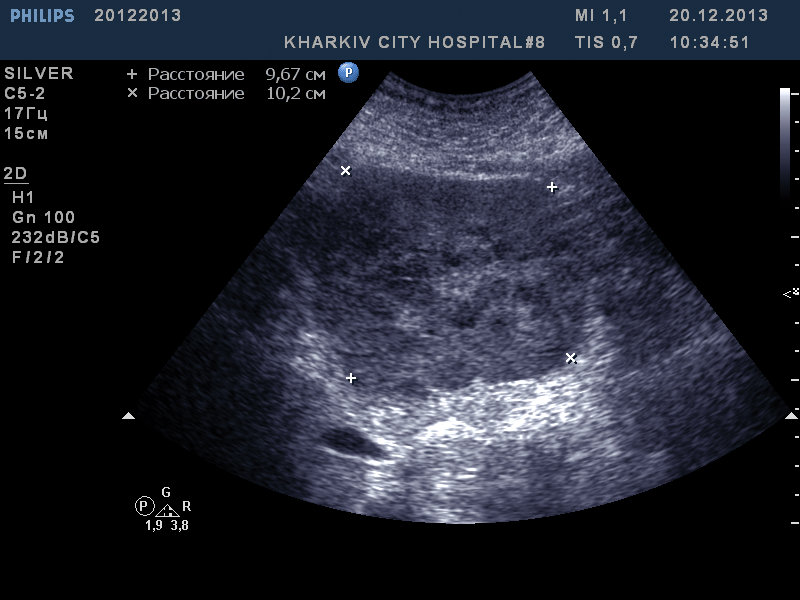

в эпигастрии в проекции левой доли данная картина. Ваши мнения?

аденокарцинома? очаговая узловая гиперплазия вряд ли

Что-то не очень хорошее.

КТ с контрастированием, бипсия.